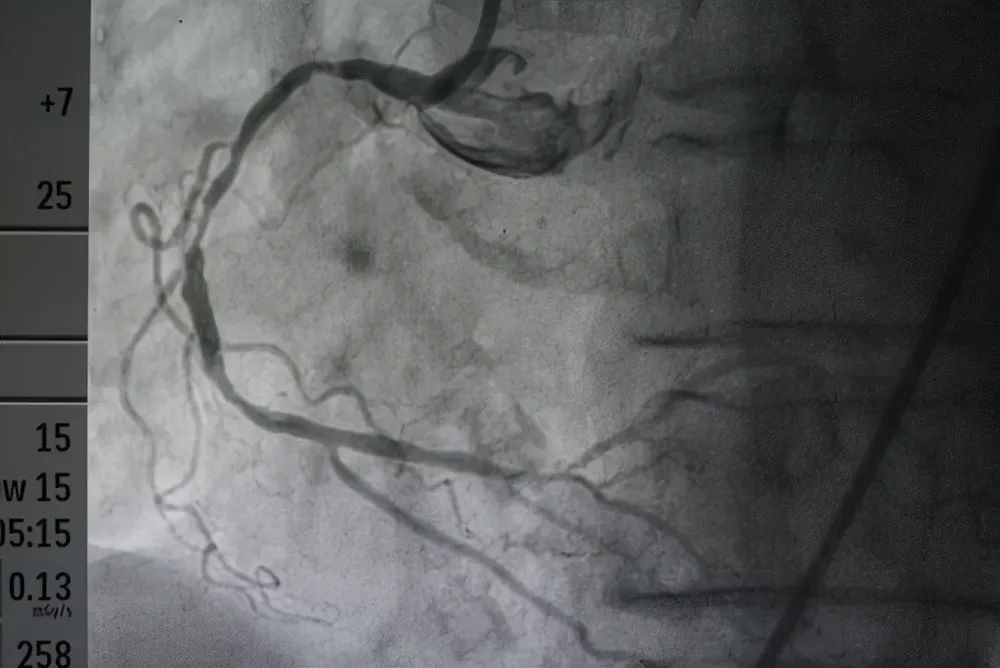

如果非要说必须准确的发现冠心病,那么就需要去做冠脉CTA或冠脉造影。

但我们常规查体,肯定没有必要做这些检查,因为这两个检查本身有辐射,且要使用造影剂,对身体有一定的风险。只有当高度怀疑冠心病的时候,才需要在医生指导下完成冠脉CTA或冠脉造影。